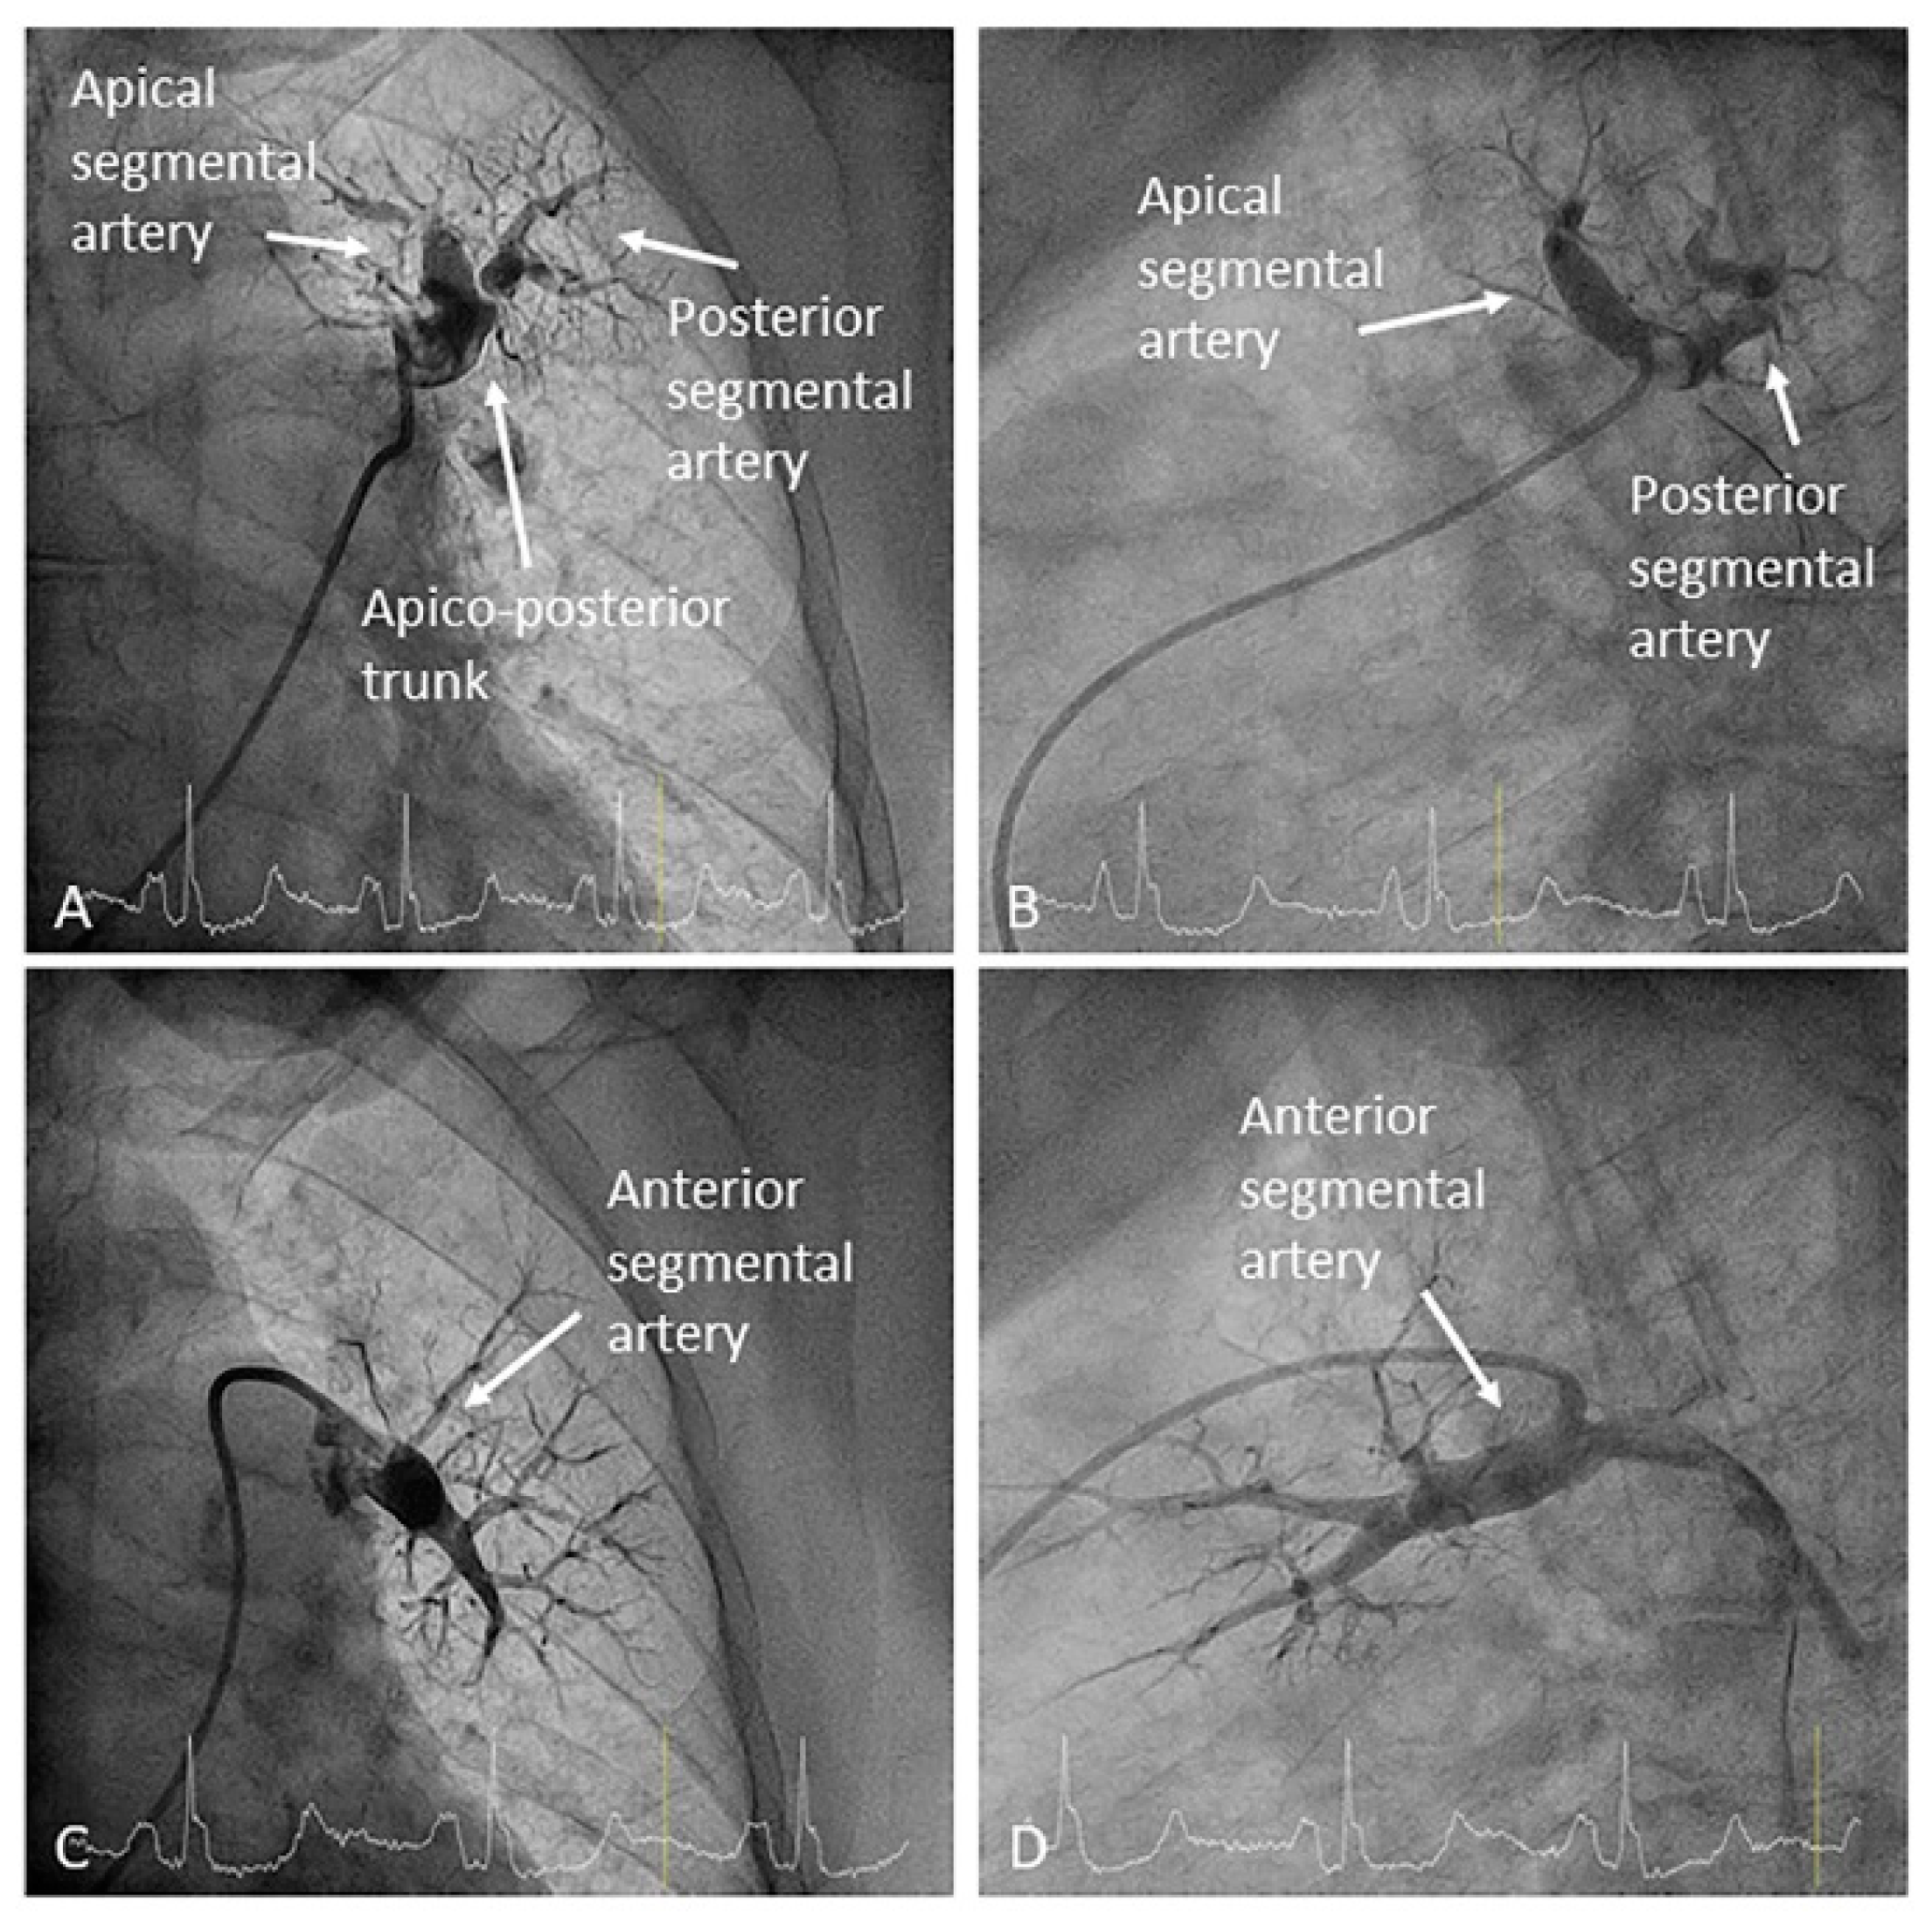

- Left upper lobe. The apico-posterior trunk (A1/2) is easily cannulated in the AP view. We should rotate the MP-A2 catheter counterclockwise in the proximal segment of the LPA to make the tip face upwards (Figure 23). The apical and posterior segmental arteries (A1 and A2) are well visualized by filming in the AP and lateral views. The anterior segmental artery (A3) is engaged more easily with the Judkins left catheter (JL) 3.5 or 4. Position the JL below the aortic arc in the AP view with the distal tip facing the left lateral chest wall. Rotate the catheter counterclockwise and withdraw it slightly. The distal tip of the catheter will climb 2–3 cm, engaging the anterior segmental branch (A3) (Figure 24). Film this branch in the cranial RAO and lateral views.

- Right upper lobe. The right upper lobar artery arises about 10 cm from the bifurcation. It is cannulated in the AP view with the tip of the MP-A2 facing upwards. The apico-posterior segmental artery (A1/2) is canalized just by advancing the MP distally once in the right upper lobe artery. The AP and lateral views display the apical (A1) and posterior branches (A2) (Figure 28). The anterior segmental artery (A3) is canalized in the lateral view, rotating the MP counterclockwise from its position in the apico-posterior artery (A1/2). With this maneuver, the tip of the catheter moves downwards, facing the sternum and engaging the anterior segmental artery (A3) (Figure 29). This branch should be filmed in lateral and cranial AP/cranial LAO view.